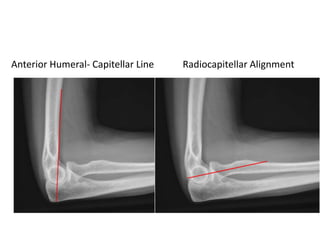

Measurements on Lateral Radiograph

1. Anterior Humeral- Capitellar Line.

2. Radiocapitellar Alignment.

Anterior Humeral- Capitellar Line Radiocapitellar Alignment